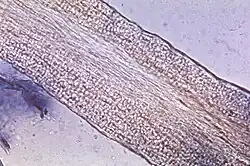

Mikrokonidia różnej wielkości, produkowane w dużych ilościach, utworzone na luźno skupionych gałęziach lub pogrubionych strzępkach końcowych, siedzące, maczugowate do prawie cylindrycznych, czasami napęczniałe do kształtu balononu. Makronidia, jeśli są obecne, zmienne, często nieco grubościenne, 2–6-komórkowe, cylindryczne do cygarowatych, 10–65 × 4–12 µm. W dużych ilościach, na końcach strzępek lub interkalarnie, powstają napęczniałe chlamydospory[4].